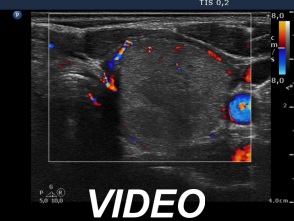

Six months after the therapy (second row of images):

Clinical presentation: the complaints of the patient have disappeared and she did not feel the lesion in the left lobe.

Palpation: the lesion in the left lobe became non-palpable.

Ultrasonography the volume of the treated nodule decreased to less than one-quarter of the original size.

Functional state: euthyroidism with TSH 1.56 mIU/L.